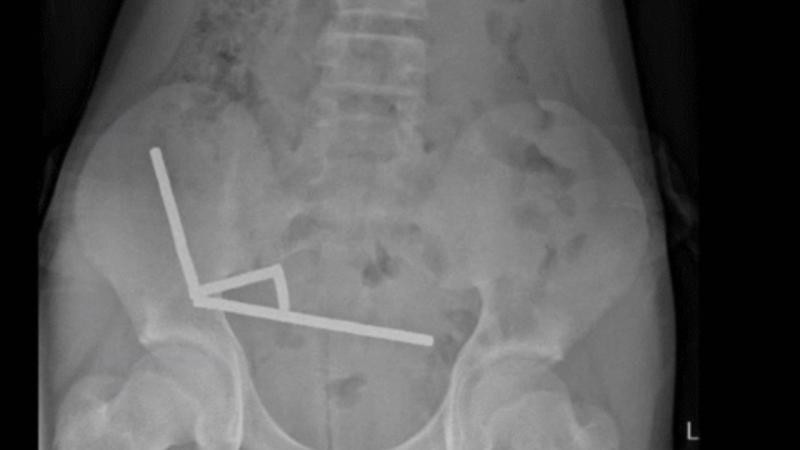

Маалым болгондой, рентген сүрөттөрүндө баланын ичегисинде төрт башка жерде чынжыр сыяктуу тизилген металлдар көрүлгөн. Алар бири-бирине жабышып, ичеги ткандарында кан айланууну токтотуп, "басым некрозу" деп аталган ткандардын өлүшүнө себеп болгон. Дарыгерлер ичегинин жабыркаган бөлүгүн кесүүгө аргасыз болушкан. Бала сегиз күндөн кийин үйүнө чыгарылган.